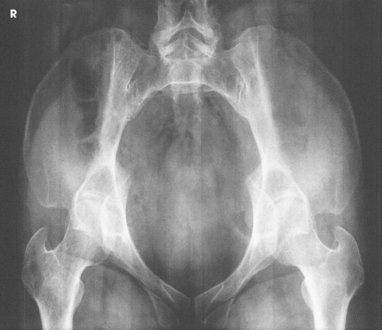

The female pelvis (Fig. 7-8) is lighter in structure than the male pelvis (Fig. 7-9). It is wider and shallower, and the inlet is larger and more oval-shaped. The sacrum is wider, it curves more sharply posteriorly, and the sacral promontory is flatter. The width and depth of the pelvis vary with stature and gender (Table 7-2). The female pelvis is shaped for childbearing and delivery.

The pelvis is divided into two portions by an oblique plane that extends from the upper anterior margin of the sacrum to the upper margin of the pubic symphysis. The boundary line of this plane is called the brim of the pelvis (see Figs. 7-8 and 7-9). The region above the brim is called the false or greater pelvis, and the region below the brim is called the true or lesser pelvis.

Structures shown: The image shows an AP projection of the pelvis and of the head, neck, trochanters, and proximal one third or one fourth of the shaft of the femora (Fig. 7-18).

Structures shown: The resulting image shows the head, neck, trochanters, and proximal one third of the body of the femur (Fig. 7-31). In the initial examination of a hip lesion, whether traumatic or pathologic in origin, the AP projection is often obtained using an IR large enough to include the entire pelvic girdle and upper femora. Progress studies may be restricted to the affected side.